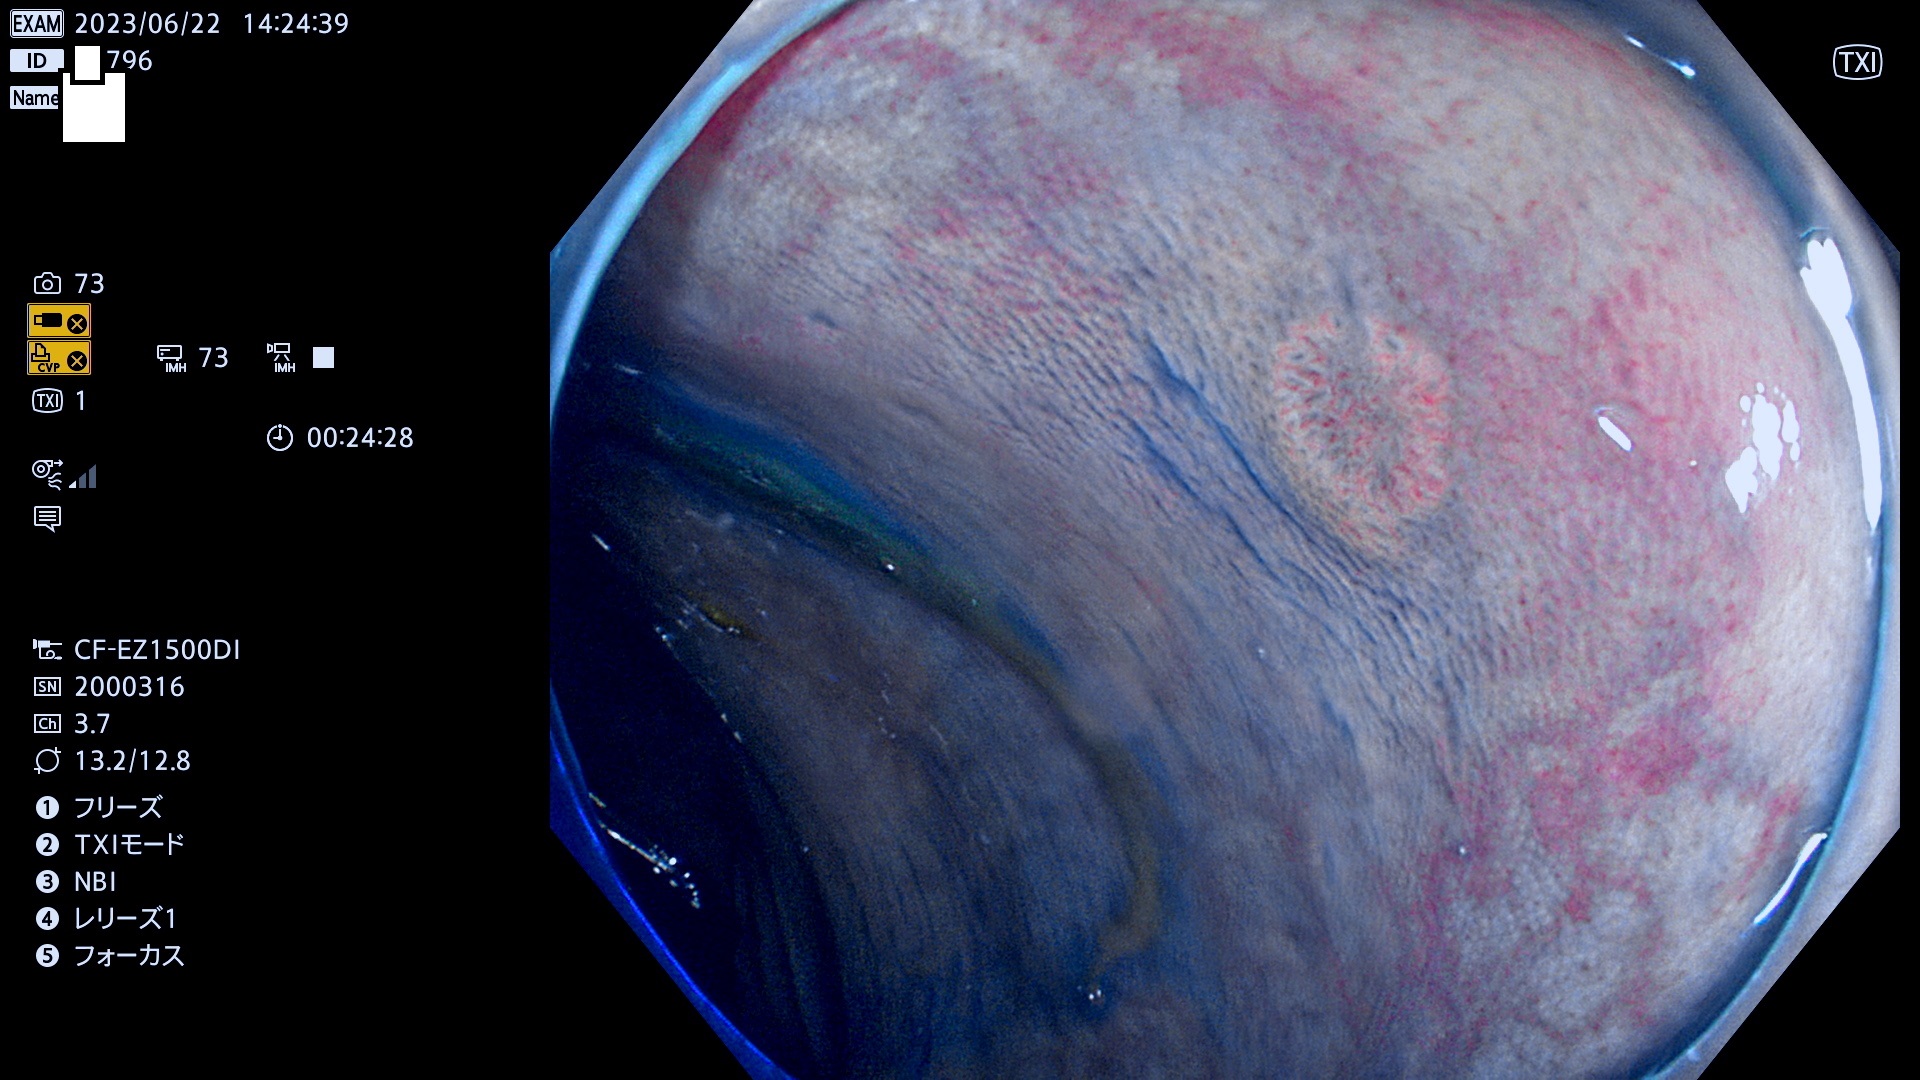

「表面型腫瘍」の中で、完全に平坦な物をUb、陥凹している物をUcと呼びます。平坦隆起型(Ua)よりも、発見が難しく危険な病変です。このタイプの発見率は「腺腫発見率」よりも、遥かに重要な意義があります。

抽出の対象期間 2023年6月22日(木)〜25(日)の4日間(48件の検査)5件

当サイトは以前は「腺腫発見率」を定期公開していました。「Ub,Uc発見率」は検査の品質指標として、遥かに重要であり、医師にとっても非常にシビアです。定期公開の目的は、検査精度の維持です。これにより医師は常に、「Ub,Ucを見つける!」という緊張感・動機をもって、検査に望む訳です(Ub,Ucを探せば、他の形態の病変は容易に見つかります。このような趣旨なので形態診断学的には厳密ではありません)。